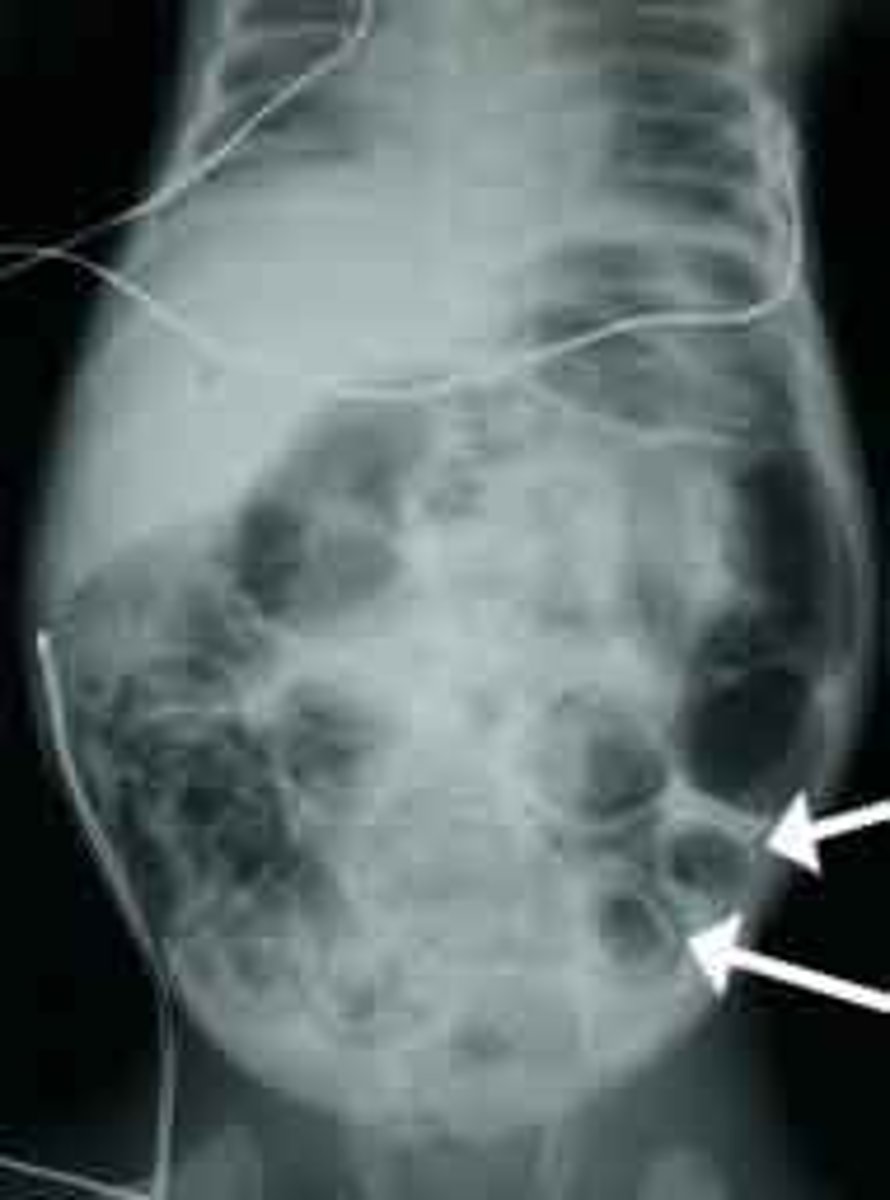

What is the best initial test to diagnose meconium ileus, & what should this be followed up by? What will be seen?

Initial: abdominal x-ray - shows multiple loops of small bowel in "soap-bubble" appearance

F/U: upper GI contrast series & contrast enema - shows microcolon inspissated w/ meconium